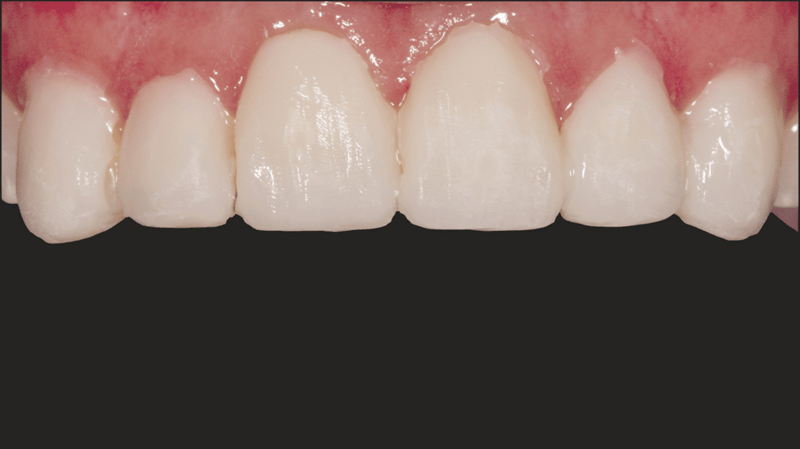

- Composite Placement: Transcend composite in B1D shade was placed starting 2/3 up from the incisal edge, gradually thinning towards the gingival area. The Universal Body (UB) shade was applied near the gingival 1/3, with final layers using Enamel White (EW) and a small amount of UB at the gingival margin for natural blending.

- Cementation Results: The final cementation resulted in a stable and esthetically pleasing veneer placement.

- Facial Anatomy: To develop the facial anatomy, football diamond and long, thin diamond burs were used. A lobed diamond bur was used to create the lines of Retzius (SR lines). The initial polishing was completed with Jiffy™ Natural polishers, then the final luster was achieved with Ultradent™ Diamond Polish Mint and the Jiffy™ Goat Hair Brush (not available in Europe) to not remove the tertiary anatomy.

The procedure successfully addressed the patient’s esthetic concerns by masking the discoloration of her upper anterior teeth and achieving a natural, balanced look with her lower anteriors. The use of no-prep direct-bonded composite veneers provided a conservative, highly effective solution that respected both the patient’s financial constraints and desire for minimal invasiveness.